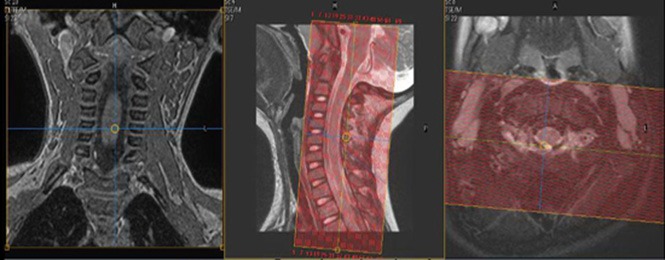

| Plane | Weighting | Mode | Slice | Gap | FAT SAT | FOV | Notes |

|---|---|---|---|---|---|---|---|

| SAG | T2 | TSE | 2.5mm | 0.5mm | None | 20cm | Include Facet Joints |

| SAG | T1 | TSE | 2.5mm | 0.5mm | None | 20cm | Include Facet Joints |

| SAG | STIR | TSE | 2.5mm | 0.5mm | None | 20cm | Include Facet Joints |

| SAG | T2 FFE | GRE | 2.5mm | 0.5mm | None | 20cm | Include Facet Joints |

| AX | T2 | TSE | 2.5mm | 0.5mm | SPAIR | 20cm | Include Facet Joints |

| AX | T1 | TSE | 2.5mm | 0.5mm | None | 20cm | Include Facet Joints |

| COR | T2 | TSE | 2.5mm | 0.5mm | SPIR | 20cm | Include Facet Joints |